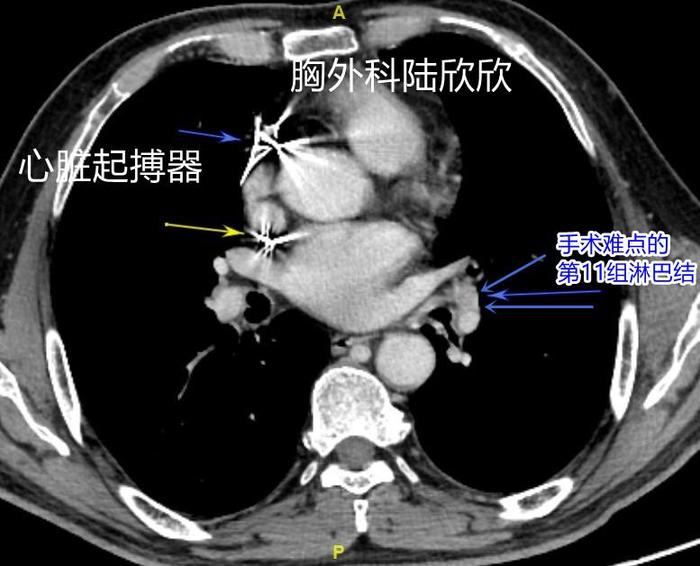

上图,心脏里面发亮的是心脏起搏器,3个蓝色箭头指示的是上下叶支气管夹角的淋巴结。淋巴结后面发白的圆形结构是左下肺的动脉这个淋巴结虽然病理证实没有转移,但是手术中切除困难。

胸腔镜手术中因为有心脏起搏器,使用电刀,腔镜用的电凝钩受到限制。肿瘤大小约57×46×50mm,距离肿瘤15毫米左右有一大片实变的肺组织,如果把肿瘤和这块发炎的肺组织看作一个整体,那么肿瘤+炎症的的病变区域最大径大约85毫米左右,从胸腔镜的切口中拿不出来,最后只好延长切口2厘米,采取多种手段,很不容易把左下肺拿出体外。